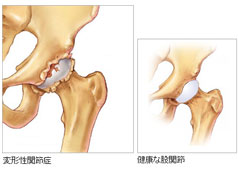

元々このJSNXは、私がスキー時代に痛めていたために、その後股関節変形症となった左股関節を治療・保護するために私自身が開発し、それをゴルフへ応用したものです。JSNXを確立してからは、フィジカル面でのコーチングとしてジュニア育成、トッププロの身体メンテナンスに活用しています。

股関節変形症はスキーでアイスバーンしたときに強打した左中殿筋(ひだりちゅうでんきん)が潰れてしまい、そのため、大殿筋(だいでんきん)が代償動作という、かばう動きが強くなってしまっていたために、股関節の軟骨に負担がかかり、すり減ってしまった結果でした。

股関節変形症はスキーでアイスバーンしたときに強打した左中殿筋(ひだりちゅうでんきん)が潰れてしまい、そのため、大殿筋(だいでんきん)が代償動作という、かばう動きが強くなってしまっていたために、股関節の軟骨に負担がかかり、すり減ってしまった結果でした。

実際、2つの病院から手術するよう進められたのですが、JSNXによるトレーニングで普通にゴルフが出来るようにまでなりました。さらに言えば、身体に無理のないショットができるようになったのです。手術も回避することが出来ました。このJSNXは、多くの方の末永いゴルフライフに役に立つものと確信しています。

この教材で講師をつとめている私、大森睦弘は左股関節変形症で、股関節置換手術をするように医者から今でも言われています。しかし、できれば一生自分の股関節を使い続けることができればと考えて生まれたのがこのエクササイズだったのです。その具体的な内容とは?